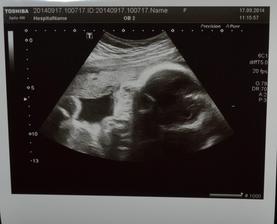

+ 17.9. - 33tt - dnešní kontrla opět v pořádku - čípek OK, vody dostatek, stěry, moč a krev jsou v pořádku. Ellinka má 1810g (je moooc šikovná). Paní doktorka měla před obědem čas, tak udělala fotečky a i jednu 3D 🙂 Ode dneška jsem na mateřské dovolené 🙂